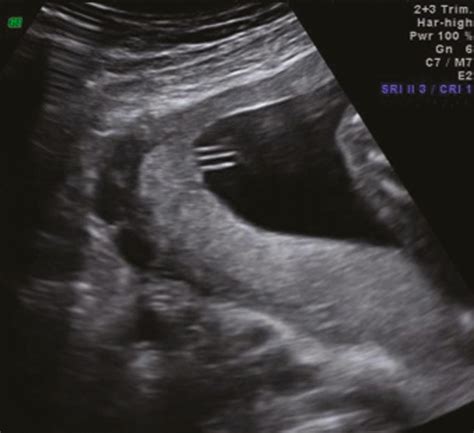

The most common way to identify marginal cord placement is through routine obstetric ultrasonography. During your mid-pregnancy anomaly scan—typically performed between 18 and 22 weeks—a sonographer will examine the placenta to ensure it is developing healthily. They will look specifically at the insertion point of the umbilical cord to determine whether it is central, marginal, or velamentous (where the cord inserts into the membranes rather than the placenta itself).

Because the condition is usually asymptomatic for the mother, you would not know it is present without this imaging. If your provider identifies a marginal insertion, they may simply document it in your chart and keep a closer eye on fetal growth during your subsequent visits.